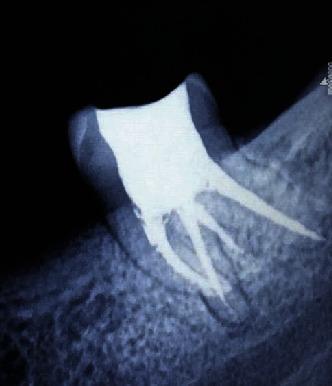

The success of endodontic therapy is attributed to complete arbitration of the bound entities concealed within the complexity and absolute disinfection of the root canal system, thus, deeming it mandatory to effectively negotiate and overcome the challenges posed by obstruction, either iatrogenic or anatomic. To achieve this, considerable depth of knowledge and expertise with reference to variations in root canal morphology and clinical mishap management is substantially as important as developing fine observation skills in conjunction with an appropriate armamentarium and a keen sense of determination, thereby enhancing one's clinical acumen by several folds. In the present case, following rubber dam isolation, the temporary restoration was removed, and the remaining carious dentin was excavated. Endodontic access cavity was refined and explored with a DG-16 probe, following which three separate canal orifices were identified in the pulp chamber floor (mesiobuccal, mesiolingual, and distal). On further observation under a surgical operating microscope and continuous exploration with the DG-16 probe, a fourth canal was found in the mesial aspect of the tooth (middle mesial). With instrumentation, it was confirmed that a fractured object was indeed present at the apical third of the mesiolingual root of tooth 38. Bypassing of the fractured fragment was initiated with a size 10 SS K-file coupled with copious irrigation with 3% sodium hypochlorite. In the present case report, four distinct canals comprising 3 mesial and 1 distal canal were recognized, and the fractured instrument in one of the canals was bypassed successfully.

根管治疗的成功归因于对隐藏在根管系统复杂性中的相关实体进行彻底清理以及对根管系统进行彻底消毒,因此,必须有效应对并克服由医源性或解剖学原因造成的阻塞所带来的挑战。要做到这一点,对根管形态变异和临床失误处理方面有相当深入的知识和专业技能,与培养敏锐的观察技巧、配备合适的器械以及坚定的决心同样重要,从而使临床敏锐度提升数倍。在本病例中,在橡皮障隔离后,去除了临时修复体,并挖除了剩余的龋坏牙本质。用DG - 16探针修整并探查根管入口洞形,随后在髓室底发现了三个独立的根管口(近中颊侧、近中舌侧和远中)。在手术显微镜下进一步观察并继续用DG - 16探针探查时,在牙齿的近中面(近中中部)发现了第四条根管。通过器械操作,证实38号牙近中舌根根尖三分之一处确实存在一个折断的物体。先用10号不锈钢K锉绕过折断碎片,并辅以大量3%次氯酸钠冲洗。在本病例报告中,识别出了四条不同的根管,包括3条近中根管和1条远中根管,并且成功绕过了其中一条根管内的折断器械。